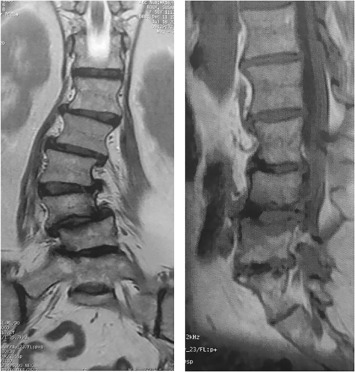

الأشعة السينية (X-ray): لتحديد درجة الانحناء وشكله.

التصوير بالرنين المغناطيسي (MRI): للكشف عن مشاكل الأعصاب أو انزلاق الأقراص.